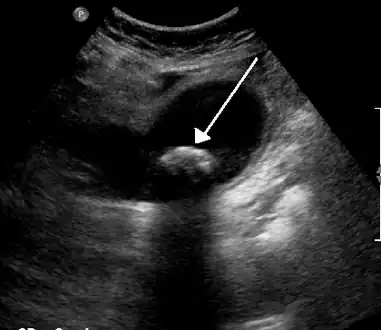

Biliary colic is often related to a stone in the gallbladder

Diagnosis is guided by the person's presenting symptoms and laboratory findings. The gold standard imaging modality for the presence of gallstones is ultrasound of the right upper quadrant. There are many reasons for this choice, including no exposure to radiation, low cost, and availability in city, urban, and rural hospitals. Gallstones are detected with a specificity and sensitivity of greater than 95% with ultrasound.[18] Further signs on ultrasound may suggest cholecystitis or choledocholithiasis.[12] Computed Tomography (CT) is not indicated when investigating for gallbladder disease as 60% of stones are not radiopaque.[12] CT should only be utilized if other intra-abdominal pathology exists or the diagnosis is uncertain.[19] Endoscopic retrograde cholangiopancreatography (ERCP) should be used only if lab tests suggest the existence of a gallstone in the bile duct.[12] ERCP is then both diagnostic and therapeutic.